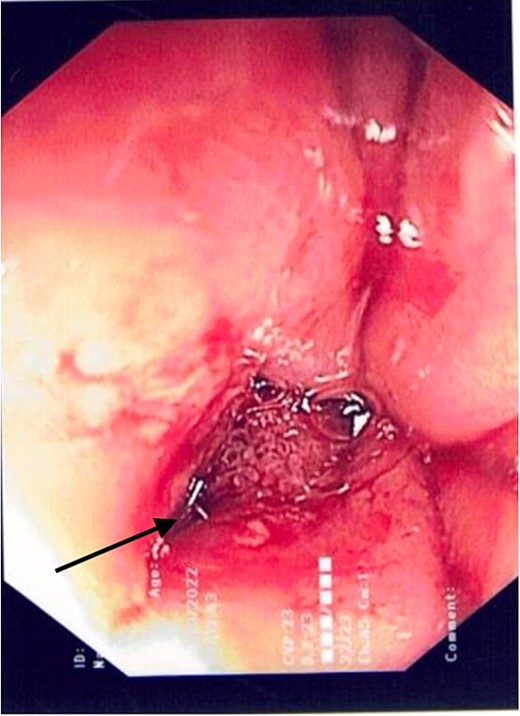

2L of pus was evacuated during laparoscopy, and it was converted to open due to limited views. At this stage, there was no obvious perforation. The entire colon was inspected, following splenic flexure and caecal mobilization. On inspection of the stomach, the wrap was intact with an unremarkable leak test. The decision was made to proceed with gastroscopy, whereby a 3 mm pinhole defect was seen at the GOJ at the 9 o’clock position, as shown in Fig. 2. Three haemostatic Cook Medical Instinct clips were placed, from distal to proximal, ensuring there was stable apposition of the perforated mucosa prior to deploying, as demonstrated in Fig. 3. Following this, the NGT was re-inserted under vision. The midline laparotomy was partially closed and Abthera dressing placed. The patient was taken to ICU intubated, with definitive closure performed 48 h later.

Gastroscopic image demonstrating the pinhole defect of the GOJ at the 9 o’clock position (arrow).